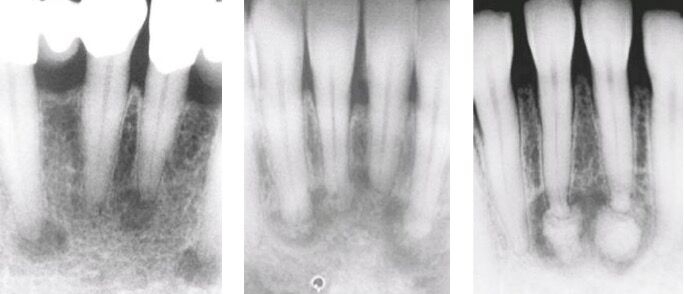

66.17歲男孩因上顎右側有一個無疼痛的腫脹而來求診,經X光檢查(如附圖)發現一個放射線不透過性影像如 箭頭所示之區域,根尖片可見到此病變與周圍界線不清楚,此病患最可能罹患下列何種疾病?

A)cementum長出來的所以會黏在牙齒上,有些會長超大坨

B)通常雙側、多處發生,可能會吃穿mucosa露出cemento-like的物質,PANO 初期看起來有點像periapical cyst後期RL的病灶中會包著RO(跟periapical cemento-osseous dysplasia一樣),不會造成bony expansion

D)好發於中年女性下顎後牙區,界限明確,中間出現鈣化組織(unilocular mixed RO/RL),可能會造成bony expansion